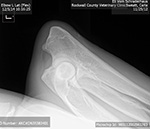

Eli's Hip films 2 years of age... Certified OFA GOOD !! ED Normal